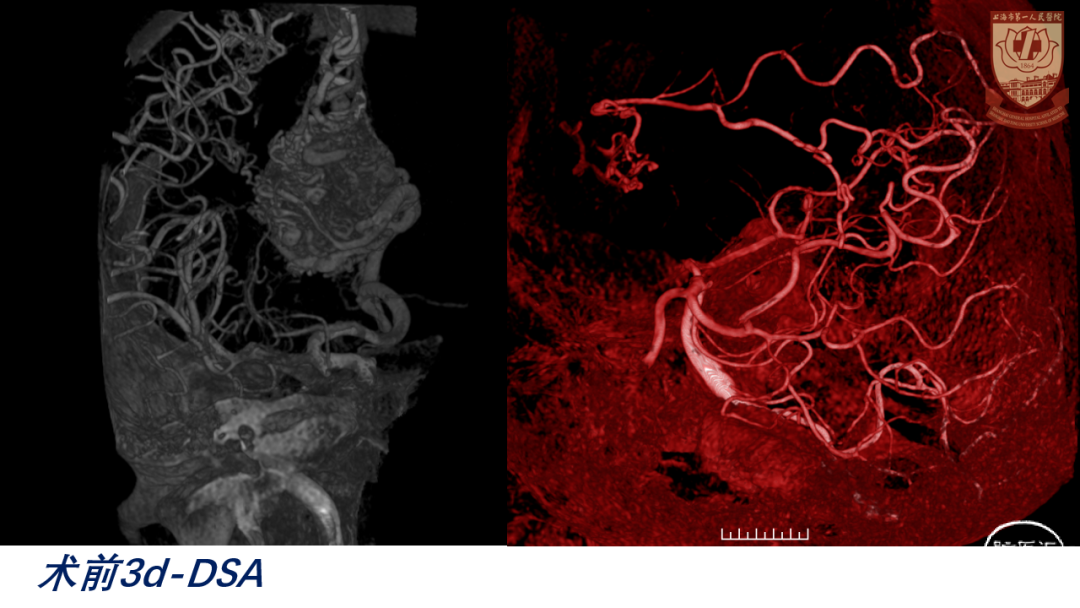

CTA、DSA:左侧额叶AVM

诊断:左侧额叶AVM破裂出血;S-M分级:IV级(S3V1E0),改良分级II级(A2B0C0)

nidus构筑

供血动脉:三组

前:左侧A3、胼缘动脉

后:大脑中动脉分支、脉络膜后动脉(后胼周动脉)

外:白质穿支动脉

引流静脉:

内侧面:额内侧静脉(前、中、后)

深部:大脑内静脉-Galen静脉